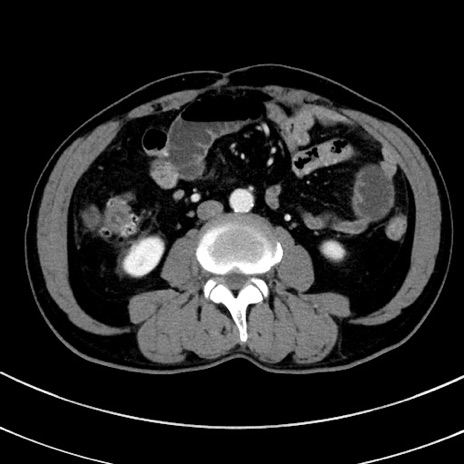

冠状断像

症例8(横断像)

【症例】 60歳代男性

【主訴】 黒色吐物

【現病歴】 4日前から嘔気自覚、2日前の朝食後にも嘔気あり、自分で手で嘔吐反射起こし嘔吐したところ血が混ざっていたため受診。

【既往歴】 5年前汎発性腹膜炎を伴う急性虫垂炎で手術、高血圧、前立腺肥大症、高脂血症

【身体所見】 腹部正中に手術癩痕あり 腹部平坦・軟圧痛なし膨満感あり

【データ】WBC 8400、CRP 4.54